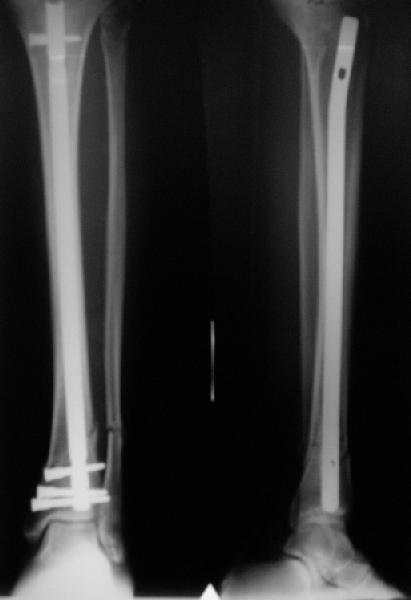

A typical case is attached, also an image with intra-op reduction obtained by a small wire distractor, in the moment of insertion a Poller wire in AP direction. Fixation by a SIGN nail. Despite the fibula was not fixed healing was obtained with the unchanged alignment.

Very interesting application, but is the final position in a little distal varus with some fibula

distraction? Would that have been eliminated by fibula plating?

At least both the ankle mortise and tibial alignment look acceptable, don't they?

I am just trying to illustrate that prevention of 1)tibial valgus and 2)loss of reduction can be provided without fibular plating. Small changes of conventional nailing techniques allow to maintain reduction of the tibia reliably without adjunctive fibular stabilization.

In delayed cases acute length restoration performed only in the tibia may leave the fibula shortened thus change the mortise. So it is reasonable to restore length of both bones simultaneously by distractor and fix the fibula not with open reduction and plating but just by a single perQ screw. Example attached.